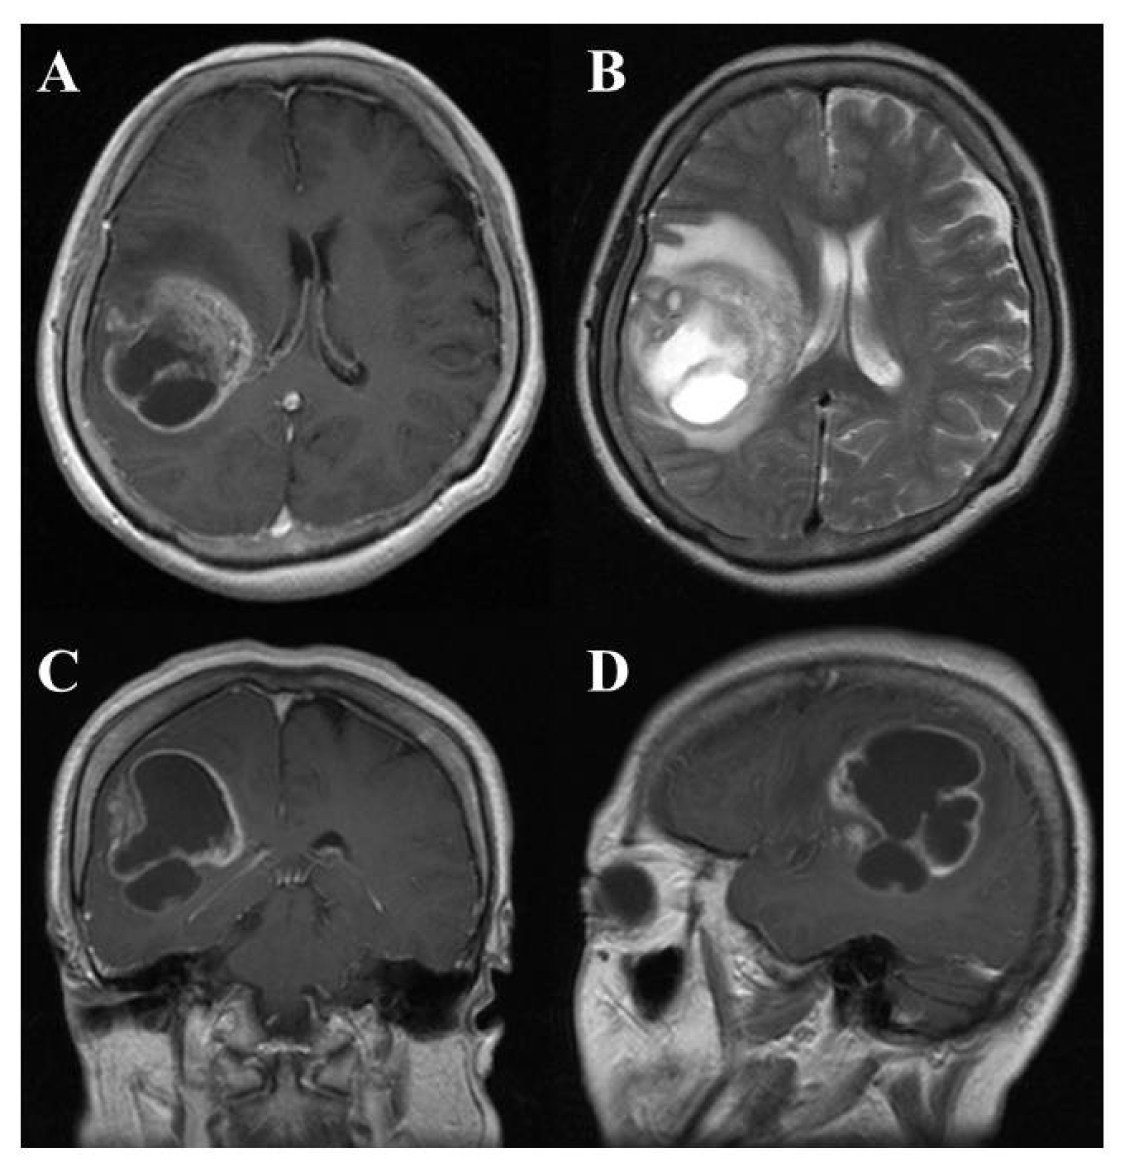

On computed tomography (CT) and magnetic resonance imaging (MRI), many GBMs present a typical appearance of ring enhancement indicating a central necrosis surrounded by enhancing viable tumor (Figure 1). Peritumoral edema, usually with distortion of the surrounding brain and ventricles (mass effect), is well visualized by MRI. Despite the typical appearance, other enhancing lesions within the cerebral hemisphere, especially abscess, metastasis, lymphoma, or even acute multiple sclerosis plaques and subacute infarctions, should be considered as notable differential diagnoses.